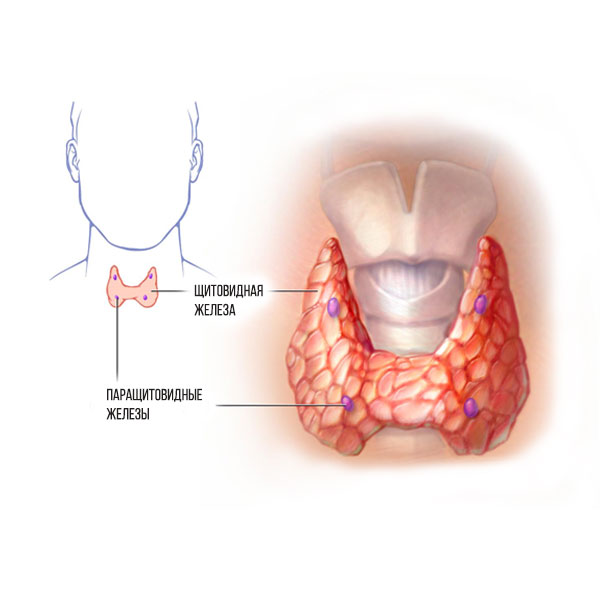

Иллюстрации и схемы по остеопорозу и паращитовидной железе